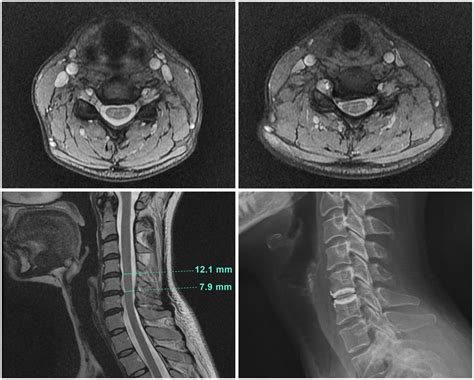

When you experience persistent neck pain, radiating discomfort into your arms, or unexplained numbness, your physician may recommend an MRI of the cervical spine. This advanced diagnostic imaging tool is the gold standard for visualizing the delicate structures of your neck, including the spinal cord, nerve roots, and the vertebrae themselves. Unlike X-rays, which primarily show bones, an MRI uses powerful magnetic fields and radio waves to create detailed, cross-sectional images of both hard and soft tissues. Understanding what this procedure entails can help alleviate anxiety and ensure you are prepared for your appointment.

The cervical spine comprises the top seven vertebrae of your spinal column, labeled C1 through C7. This area is highly complex and functionally vital, as it protects the spinal cord and allows for a wide range of head and neck movement. An MRI of the cervical spine provides a comprehensive view of several critical components:

Doctors order this scan to investigate symptoms that suggest nerve compression or structural abnormalities. It is a highly sensitive diagnostic tool that helps differentiate between various conditions. Common reasons for ordering this scan include:

• Spinal Stenosis: The narrowing of the spinal canal, which can put pressure on the spinal cord.

The primary advantage of using an MRI of the cervical spine over other imaging modalities is its superior soft-tissue contrast. Because the spinal cord and nerve roots are essentially soft tissue structures, standard X-rays are largely ineffective at visualizing them. By utilizing contrast agents in some cases, radiologists can also identify inflammation or vascular issues that are not visible on plain films. Furthermore, MRI involves zero ionizing radiation, making it a safer long-term option compared to repeated CT scans or X-rays.